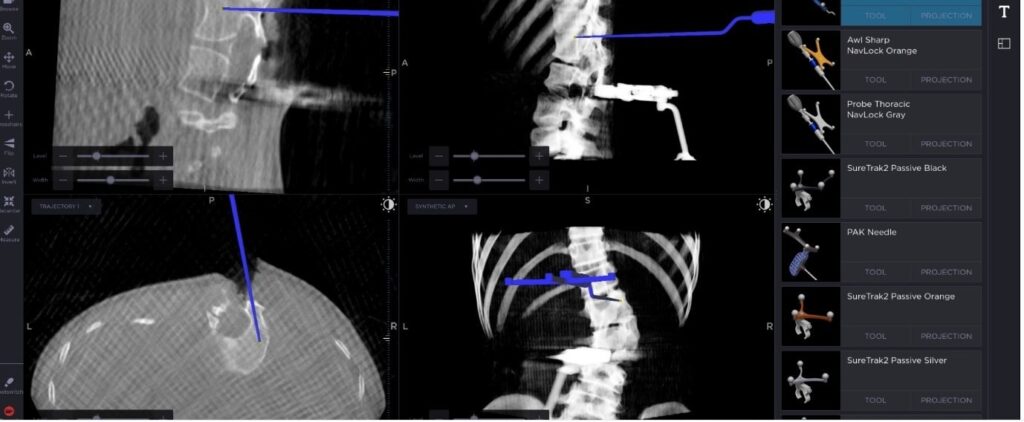

The next step was to decide on the plan for her scoliosis treatment in Ahmedabad. Considering her condition, surgical treatment was imperative to prevent the progression of scoliosis in the child. After careful analysis and discussion with the child’s parents, a successful hemivertebra excision, unilateral fixation, and fusion surgery were done with good kyphoscoliosis correction. The whole complex surgical procedure was made simpler and 100% precise by Dr Tarak Patel’s experience in the field and with help of high end technologies like intraoperative OARM and Navigation.